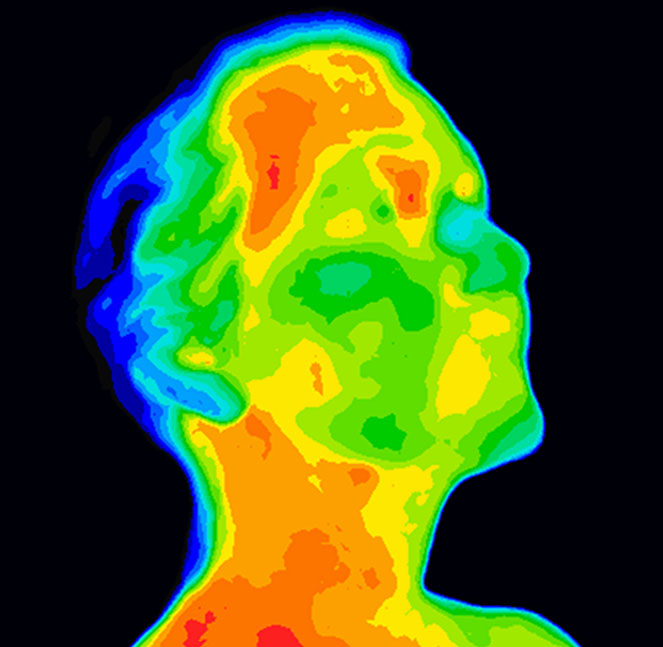

Температура объекта может быть определена по количеству инфракрасной энергии, излучаемой этим объектом, если его излучательная способность известна. Инфракрасное излучение, излучаемое человеческим телом, обычно имеет максимальную длину волны около 9 мкм. Изменения температуры приводят к изменениям исходящего инфракрасного излучения, что позволяет тепловизионным системам определять, когда температура тела субъекта выходит за пределы нормального диапазона.

Измерение инфракрасного излучения для определения температуры тела человека